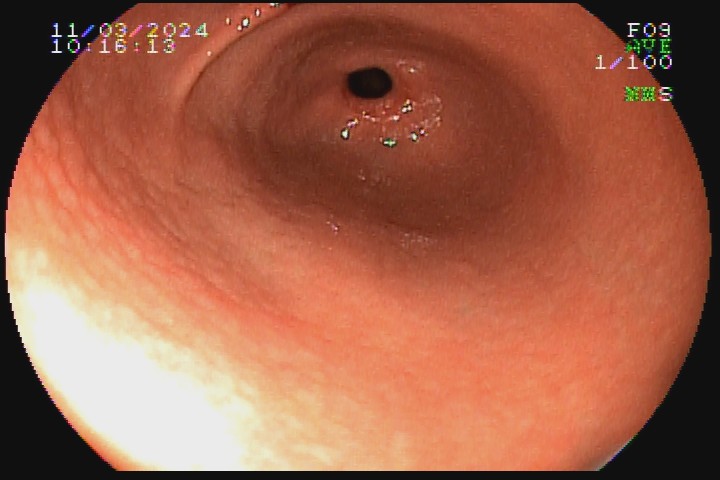

A gastrite por Helicobacter pylori é uma das formas mais comuns de gastrite. Apesar de o diagnóstico ser realizado por histologia, teste da urease, sorologia ou teste respiratório de ureia marcada, há sinais endoscópicos que possibilitam forte suspeita de positividade ou negatividade dessa infecção. Os sinais  de positividade são: enantema difuso, edema da mucosa, enantema purpurifotme, pregas alargadas e tortuosas, nodularidade, pólipo de hiperplasia foveolar, xantelasmas, muco aderido à mucosa, atrofia e metaplasia intestinal.

Os achados com mais forte correlação negativa com a infecção da mucosa gástrica por H. pylori são: presença de pólipo de glândula fúndica, presença de arranjo normal de vênulas coletoras na pequena curvatura do corpo distal e incisura angular, presença de hematina, enantema em faixa, múltiplas placas achatadas esbranquiçadas em corpo e fundo e erosões elevadas.

Veja abaixo algumas imagens do nosso acervo que demonstram gastrite com infecção pelo Helicobacter pylori comprovada no histopatológico.